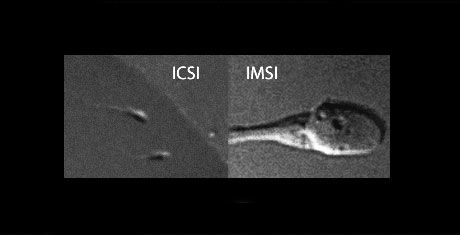

Dans le cadre de la fécondation in vitro, la technique la plus courante est la fécondation ICSI, à savoir le transfert d’un spermatozoïde dans l’ovule par injection. Le choix du spermatozoïde spécifique s’effectuait, jusqu’à présent, par grossissement de 400 à 600 fois au microscope. Cette technique permet l’observation des caractéristiques morphologiques de base du spermatozoïde, afin de sélectionner le meilleur spermatozoïde en vue de la fécondation de l’ovule.

Grâce à l’utilisation de lentilles spécifiques, les microscopes pour l’IMSI permettent de grossir les spermatozoïdes jusqu’à 10 000 fois, ce qui permet d’observer l’intérieur de la tête, rendant visibles beaucoup plus de caractéristiques.